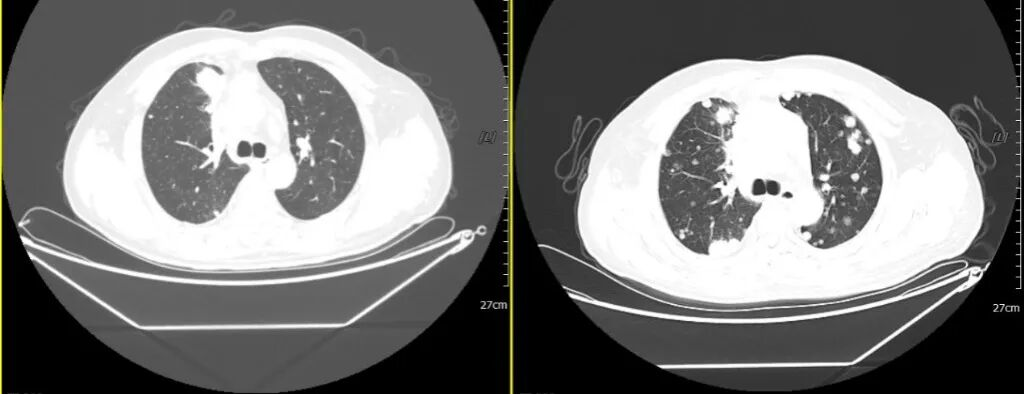

2020-07-03 2021-02-20

与2020年7月3日片对比:两肺多发异常结节较前明显增多、增大(原约3.2×2.1,现约3.9×3.0cm);纵膈前间隙、纵隔内及两肺门多发增大淋巴结较前部分增大(原约5.2×3.4,现约6.7×4.0cm)并胸骨受累(新出),邻近上腔静脉及左头臂静脉受累较前加重。